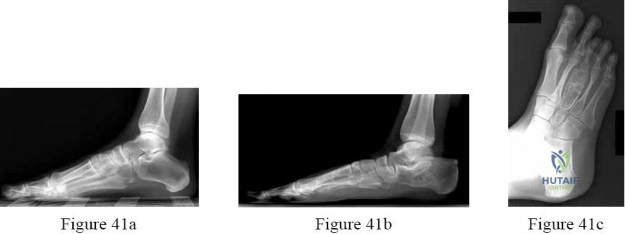

Question 41

A 55-year-old female presents with medial ankle pain and a progressively flattening arch. She has pain with single-limb heel rise but is able to perform it weakly. Passively, her hindfoot corrects to neutral. What is the most appropriate surgical intervention if conservative management fails?

Explanation